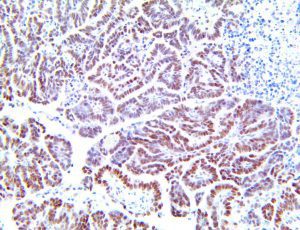

It is the ICU physician who is most likely to witness one of the deadliest manifestations of the abnormal immunological response, the cytokine storm syndrome (CSS). This response is also referred to by some as the cytokine release syndrome (CRS). CSS is characterized by continuous activation and expansion of macrophage and lymphocyte populations, which secrete large amounts of cytokines, causing the cytokine storm. This massive cytokine release is akin to hemophagocytic lymphohistiocytosis (HLH) disease, a syndrome characterized by initial unchecked and persistent activation of cytotoxic T lymphocytes and NK cells.